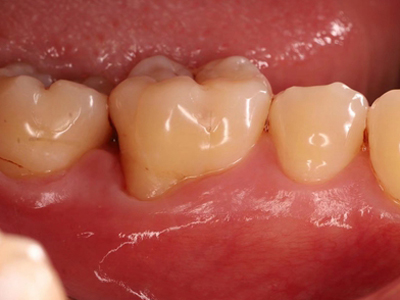

牙龈退缩露出淡黄色牙根图

牙龈退缩患者的牙龈退缩后,淡黄色牙龈明显露出。若进一步发展,易使对应位点的牙槽骨发生骨吸收,可能诱发龋齿、牙龈敏感、菌斑堆积等。